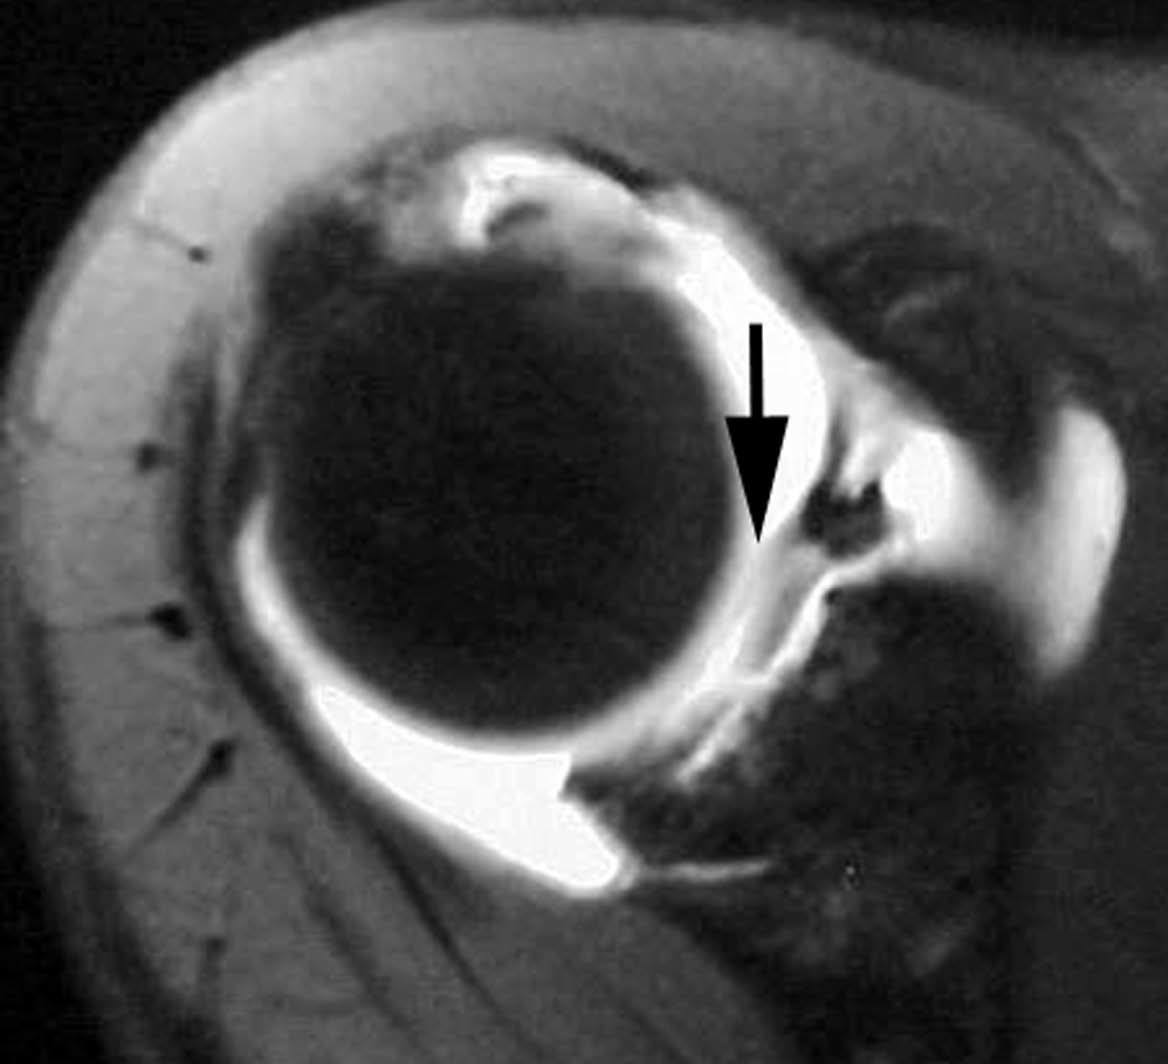

Lesión de Bankart

La lesión de Bankart se produce durante una dislocación anterior e inferior de la cabeza humeral, con impactación de la misma contra el borde anteroinferior de la glenoides, causando un arrancamiento del LG con rotura capsuloperióstica. Al mismo tiempo, se produce frecuentemente una fractura por impactación de la cabeza humeral (lesión de Hill Sachs) (fig. 9). En ocasiones, dicha lesión se acompaña de una fractura del borde anterior e inferior de la glenoides (Bankart óseo).

Fig. 9.--Lesión de Bankard y Hill-Sachs. Artrorresonancia axial T1, donde se observa un desprendimiento completo del labio glenoideo (flecha larga en A) con una rotura capsuloperióstica (cabezas de flecha en A). Nótese la fractura por compresión del margen posterosuperior de la cabeza humeral, representando una lesión de Hill-Sachs (flechas en B).